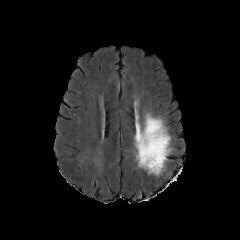

Figure 5: The results of our ablation study on the BratS18 dataset. Please see text for analysis.

Starting from the baseline GAN model, which consists of the 𝒢A2Nsubscript𝒢A2N\mathcal{G}_{\rm{A2N}} generator without shortcut and AM loss and cycle consistency, we conduct the following ablation study to validate the cycle consistency, AM loss and shortcut.

IV-B1 Evaluation of the cycle consistency

We first conduct experiments to compare the baseline GAN [8] to the same model, but with the abnormality or normality synthesis consistency penalty terms (GAN+AC and GAN+NC). In Figure 5, we show generated (i.e., fake) healthy-looking MRI produced by GAN, GAN+AC and GAN+NC. We observe that model collapse occurs in GAN and GAN+NC where the generator networks have converged to a bad local optimal solution. GAN+AC produces more meaningful image structures, however it still suffers severe artifacts due to the lack of optimizing constraints. We compare the above models with CycleGAN as a baseline state-of-the-art model for unsupervised image-to-image translation [35]. The cycle consistency term reduces the artifacts by modifying the search space. However, the gray scale shift shows some bias.

IV-B2 Evaluation of the shortcut and anomaly mask

The global shortcut connection can simplify the function mapping by forcing the generator 𝒢A2Nsubscript𝒢A2N\mathcal{G}_{\rm{A2N}} to focus on the lesion region. We compare with CycleGAN [35] and CycleGAN with a shortcut connection (CycleGAN+shortcut). The difference between CycleGAN+shortcut and our ANT-GAN is the inclusion of the anomaly mask penalty term.

In Figure 5, we observe that the generator can better detect, remove and inpaint the tumor regions without impacting the non-tumor regions by using the proposed global skip connection. However, as shown by the zoomed-in regions, CycleGAN+shortcut still performs less satisfactorily than ANT-GAN in terms of some important details of the healthy regions of the lesion-containing MRI. This is because ANT-GAN contains the anomaly mask term, which forces the generator 𝒢A2Nsubscript𝒢A2N\mathcal{G}_{\rm{A2N}} to leave healthy portions of an MRI unchanged and only detect and modify lesions. Both CycleGAN and CycleGAN+shortcut do not have this feature since they have different motivation in their design. Though based on the GAN, ANT-GAN is more motivated by image restoration than image generation.

We also use PSNR metric to further validate the benefit of shortcut and AM loss strategies in preventing non-lesion regions from distortion. The results evaluated on the testing datasests in BratS18 are shown in Table IV. We observe the proposed ANT-GAN (ANT + AC + NC + Shortcut + AM) achieves the highest PSNR value in the compared models, proving the effectiveness of the shortcut architecture and AM loss in non-lesion region preservation. The lesion regions are not amenable to objective evaluation since their ground truth healthy counterpart are unknown naturally.